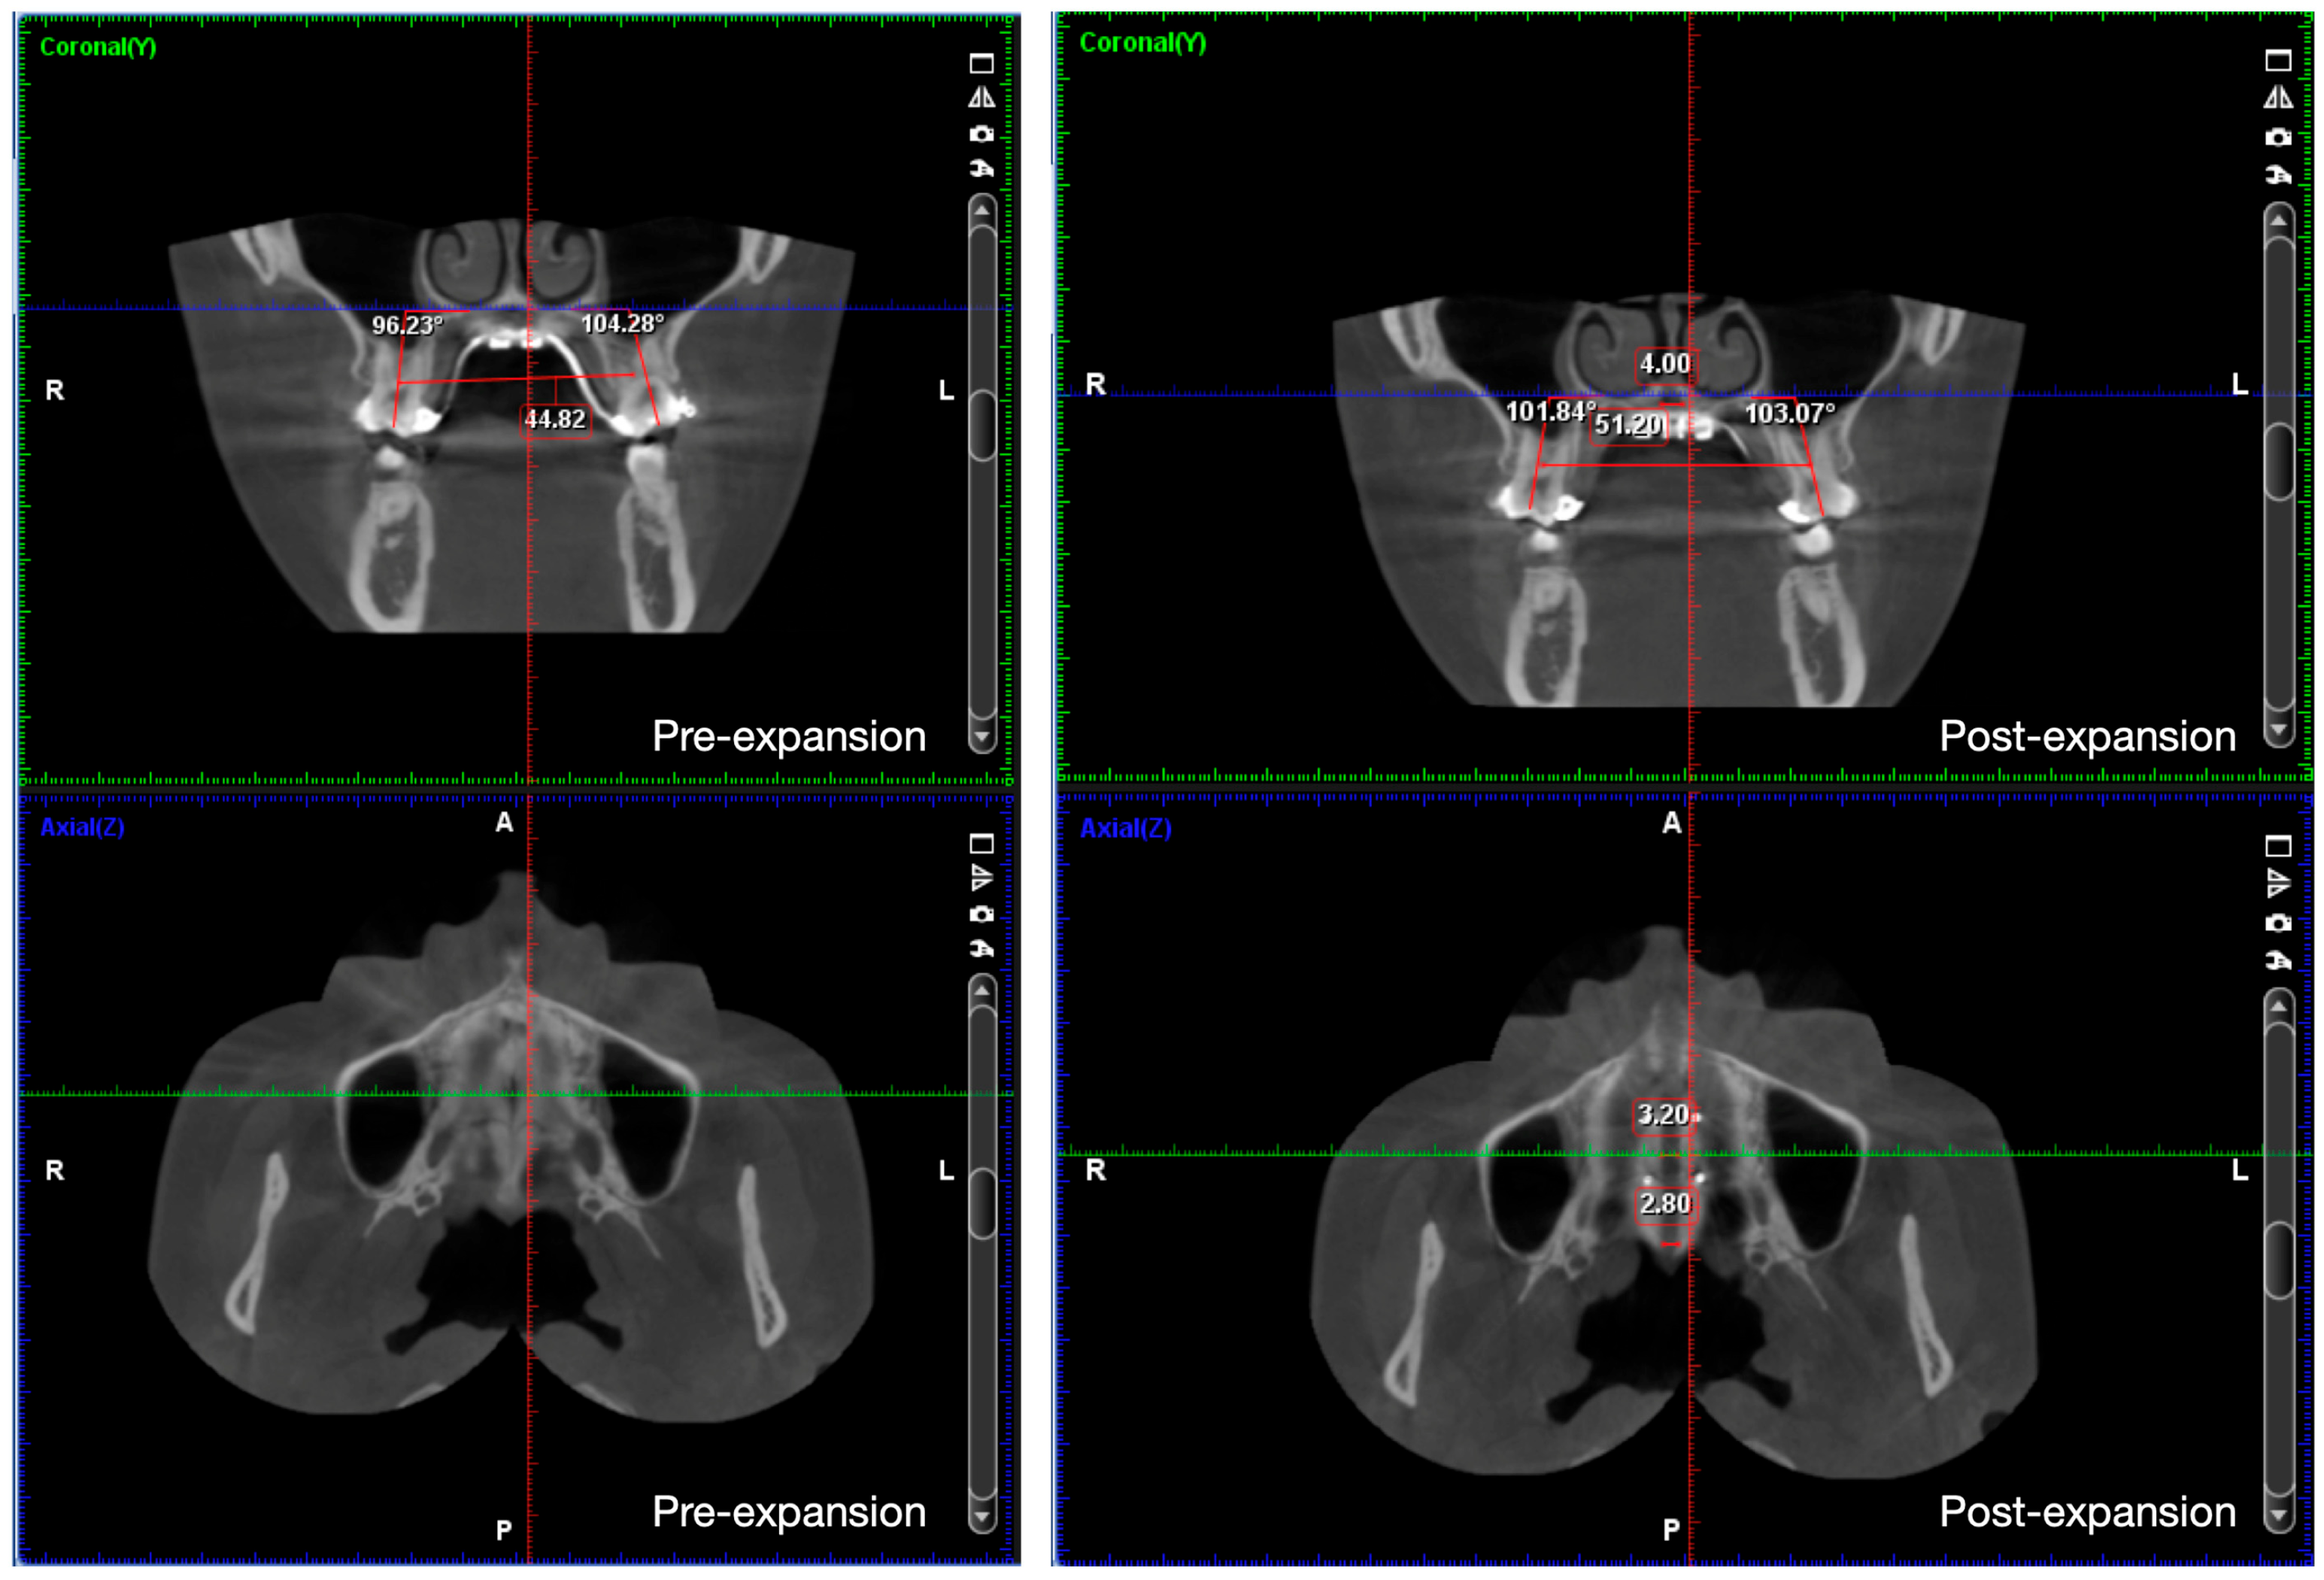

2.4. Treatment Progress

2.5. Treatment Results